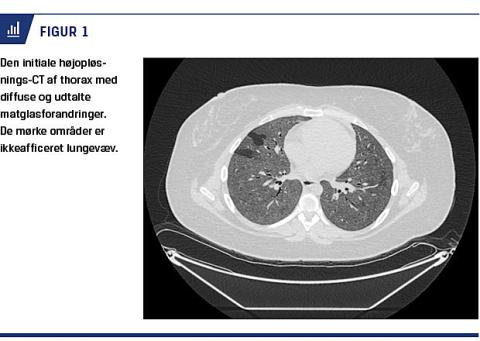

En 28-årig kvinde blev indlagt med akut forværring af dyspnø, der langsomt var progredieret året op til indlæggelsen. Patienten var gennem mange år blevet behandlet med lamotrigin for skizofreni. Røntgen af thorax og efterfølgende højopløsnings(HR)-CT viste bilaterale matglasforandringer (Figur 1), der umiddelbart blev tolket som værende forenelige med eksogen allergisk alveolitis som følge af mulig eksponering for skimmelsvamp, om end patienten ikke havde forhøjede præcipiterende antistoffer over for skimmelsvampe.